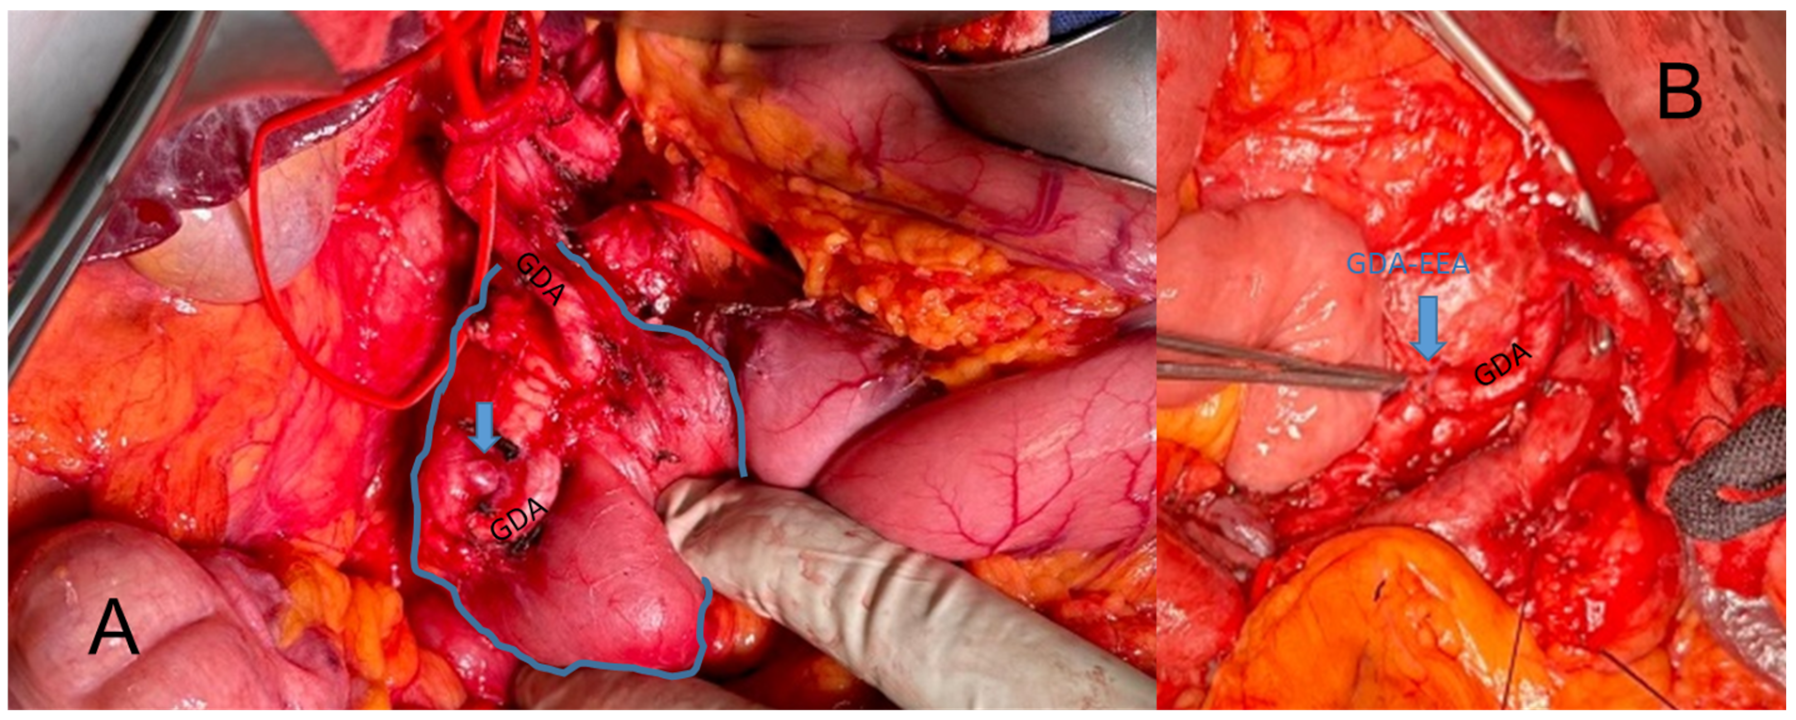

The aim of therapy was to first re-establish superior blood flow to the hepatic artery, and second, to resect or exclude the aneurysm either surgically or in a secondary procedure by coil embolization. Out of the fifteen patients undergoing surgery, seven (46.7%) were treated by a total aneurysm resection, of which six cases received an end-to-end anastomosis (one during a primary Whipple procedure due to pancreatic cancer, Figure 3A,B) of the unaffected sections of the original vessels while one patient received a venous interposition graft using a great saphenous vein graft. Three patients underwent aneurysm embolization in a secondary intervention, while two aneurysms were coil embolized during an acute rupture. In one case the aneurysm was simply ligated. Two patients with a secondary intervention for embolization also received a stent to treat the upstream stenosis (one in the celiac artery and one in superior mesenteric artery). Four patients were treated with a bypass surgery to facilitate revascularization downstream of the affected stenotic segment (three of them were aorto-hepatic including one secondary to embolization during rupture and one that was aorto-splenic). In 10 patients (62.5%) the concomitant MALC was treated by resection of the impairing soft and nerval tissues. Almost all patients received a multifaceted treatment addressing both the aneurysm and facilitating revascularization with just a single case undergoing aneurysm resection only. Treatment strategies are shown in Table 4.

Figure 3.

Intraoperative depiction of a VAPUS X A case with an aneurysm of the gastroduodenal artery (GDA) before (A) and after (B) resection and end-to-end anastomosis (EEA).